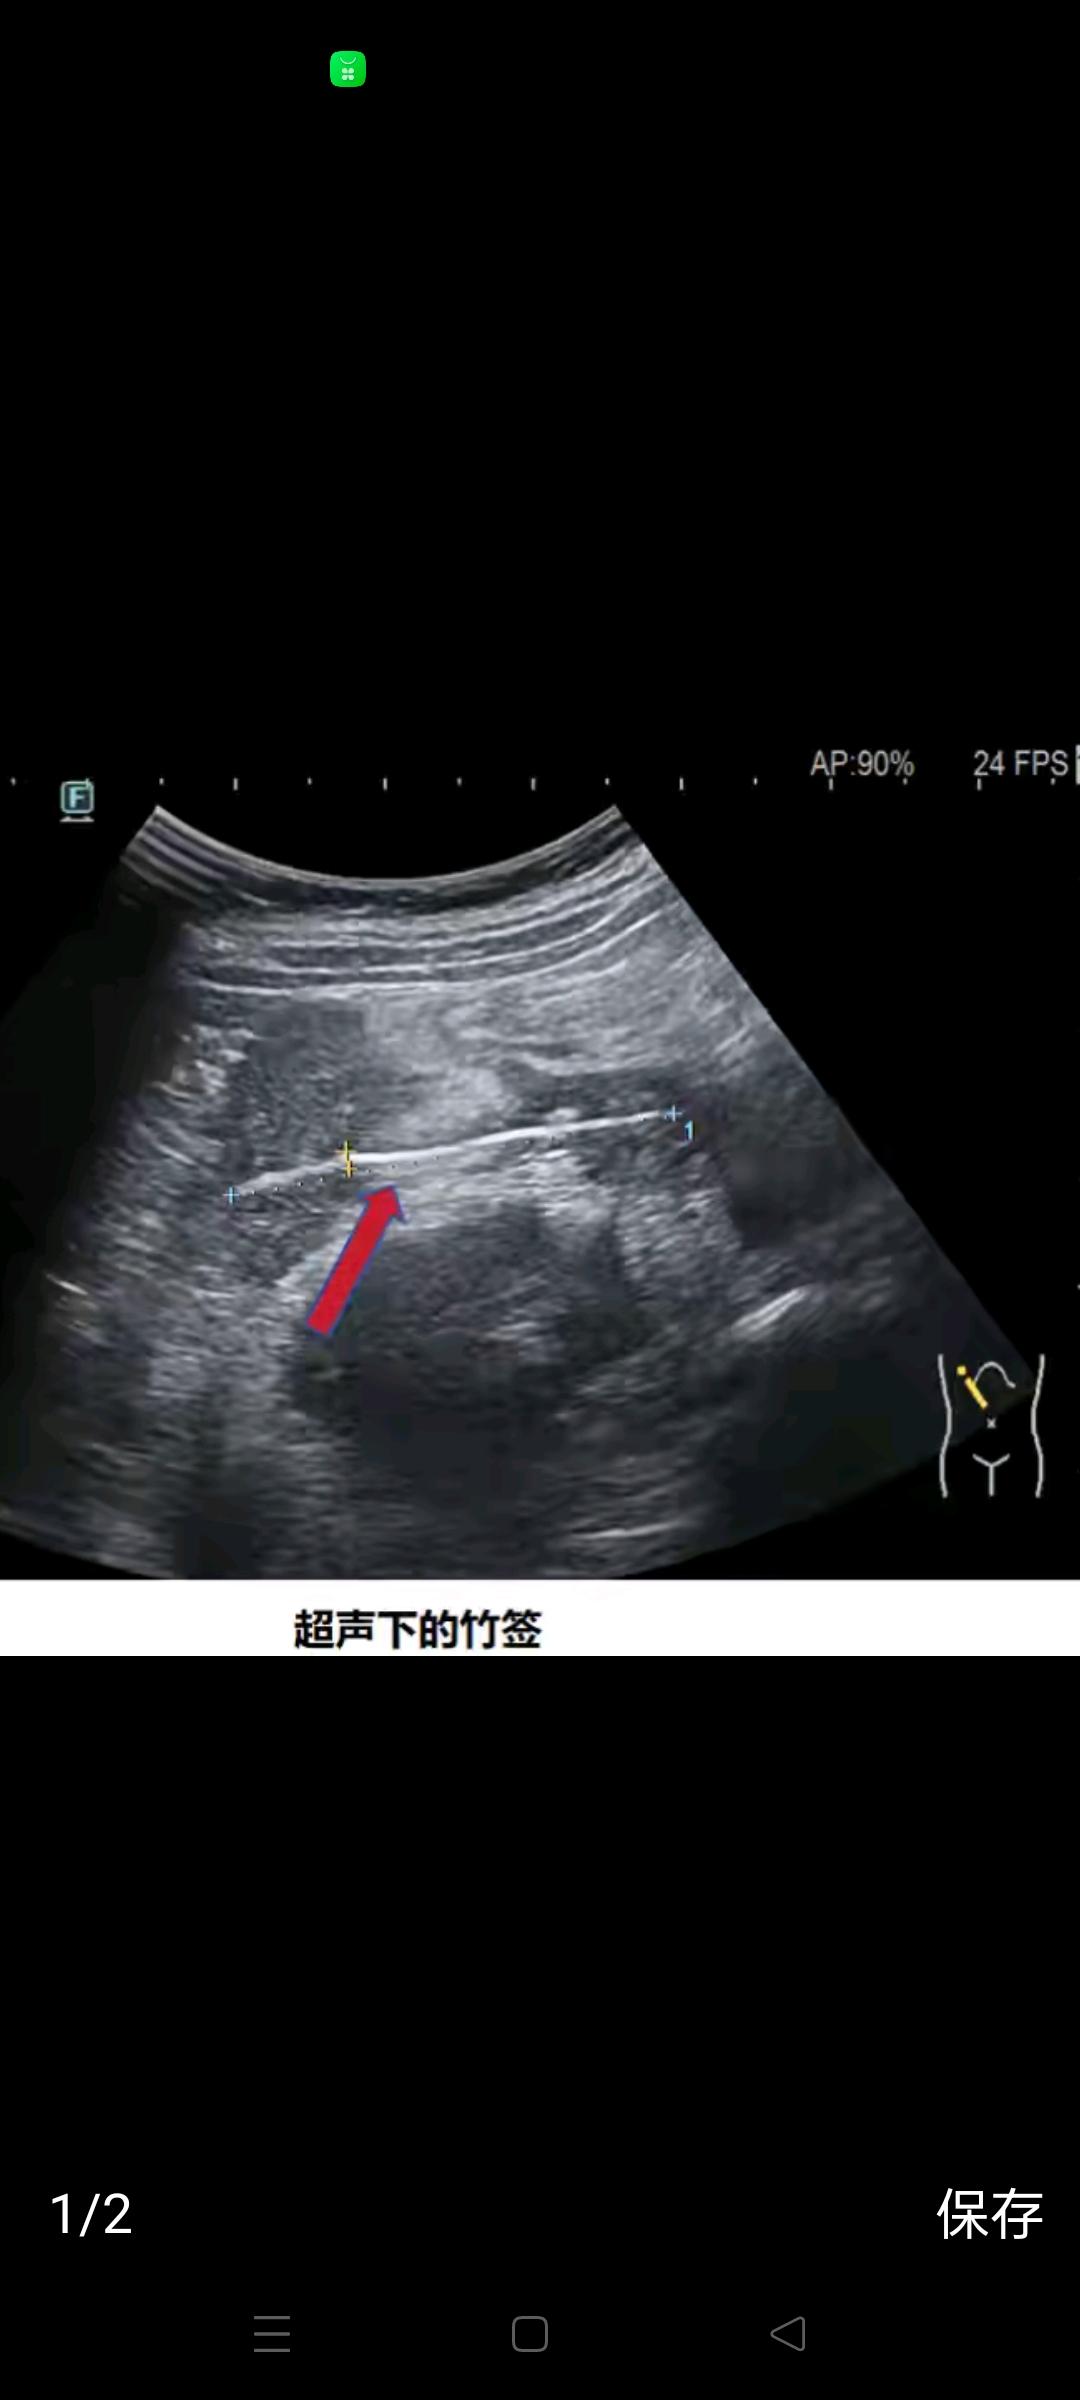

男孩吃鸡柳误吞竹签,约6厘米竹签刺穿肠道刺穿肝脏——这听起来像是一场噩梦,却真实地发生在了一个普通家庭中。一个看似寻常的午餐,竟然险些酿成无法挽回的悲剧。你能想象吗?一个孩子,因为一根小小的竹签,经历了生命的生死考验。这样的新闻,让人不禁心头一紧,也让我们不得不反思:日常生活中的安全隐患,究竟隐藏了多少我们未曾察觉的危险? 事件发生后,孩子的家长第一时间将他送往医院。医生们经过紧急检查,发现那根竹签不仅刺穿了肠道,还深深扎入了肝脏,情况极其危急。手术室里,医生们与时间赛跑,展开了一场生死救援。幸运的是,经过数小时的紧张手术,孩子脱离了生命危险,但这场意外给家庭带来的心理阴影,却远远没有那么容易抹去。 这起事件让人警醒:我们对食品安全的关注,不能只停留在“看得见”的卫生和质量上,更要关注那些看不见、摸不着的细节。竹签、牙签、塑料小叉,这些看似不起眼的小物件,往往隐藏着巨大的安全风险。尤其是对于儿童来说,缺乏足够的自我保护意识和判断能力,一旦误吞,后果不堪设想。 更深层次地说,这件事也暴露了我们社会在食品包装和餐具使用上的盲点。商家为了方便和成本,频繁使用竹签类一次性餐具,却忽视了安全提示和防护措施。我们是否应该呼吁,制定更严格的食品安全规范,尤其是在儿童餐饮领域,杜绝类似悲剧的发生? 读者朋友们,你是否也曾在用餐时遇到过类似的隐患?你是否愿意为自己和家人的安全,多一份警惕和关注?这不仅仅是一则新闻,更是一面镜子,映照出我们生活中那些被忽视的风险。关注安全,从每一个细节做起,让我们共同守护每一个孩子的健康成长。你有什么想法?欢迎在评论区分享你的故事和看法,让更多人警醒起来!蒜香脆脆炸鸡柳 油炸大鸡柳 儿童消化道异物如何处理?